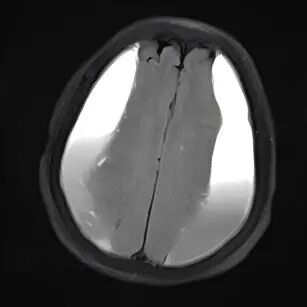

对许多老年人而言,一次轻微的头部磕碰,可能在未来几周或几个月里,悄悄引发一系列变化:走路不稳、手脚无力、记性变差,甚至性格改变,这背后,可能是一种名为“慢性硬膜下血肿”的疾病在悄然进展,它虽起病隐匿、发展缓慢,但会持续压迫大脑,影响正常功能。所幸,现代神经外科的微创手术为治疗此类疾病提供了新的选择,尤其为高龄或身体状况复杂的患者带来了新希望。 微创技术化解高龄手术难题 前不久,一名95岁的高龄患者因双腿无力、多次在家跌倒,并已无法像往常那样站立及行走,家人见状立即将老人送至贵州航天医院就医,通过影像检查发现颅内两侧都有慢性硬膜下血肿。追溯原因,竟是两个月前一次未加留意的头部轻微磕碰。 磁共振影像显示双侧颅内血肿 鉴于患者年事已高,且心肺功能不佳,神经外科团队经过细致评估,决定采用微创手术清除双侧颅内血肿。手术仅在头部开一个极小的创口,置入细软的引流管,将长期积聚的陈旧血液缓缓引出,解除大脑受压,整个过程约30分钟,创伤小,出血少。术后,患者恢复得很快,不久便能自己稳稳站立、独立行走,精神和食欲也好了很多。 疾病知识 慢性硬膜下血肿好发于大脑有一定萎缩的老年人,由于颅腔空间相对增大,头部即使受到很轻的撞击,也可能使大脑表面脆弱的静脉撕裂并缓慢渗血,血液逐渐积聚形成血肿,经过一段“潜伏期”后才压迫脑组织引起相关症状。 如果您或家中的长辈曾有头部外伤史(哪怕当时觉得不重),之后逐渐出现以下情况,请务必留心: ※一侧手臂或腿脚越来越没力气,走路易歪斜、跌倒。 ※反应比以前慢,记忆力明显减退,话变少或表达不清。 ※精神状态不佳,总想睡觉,或性格、情绪出现反常变化。 ※持续或反复的头痛、头晕。 注:本文仅为医疗技术介绍及健康科普知识分享,具体治疗方案请务必咨询临床医生,并结合患者个体情况制定。部分图片来源于网络,如有侵权,请联系删除。 贵州航天医院 神经外科专家简介 廖洪民 神经外科党支部书记、主任,主任医师 临床擅长:从事神经外科专业约30年,擅长脑部病变显微手术、立体定向手术等微创治疗。 贵州省医学会神经外科分会委员,遵义市医学会神经外科分会常务委员,遵义市中西医结合学会理事,中国生命关怀协会脑卒中救治及康复照护专业委员会委员,遵义市脑损伤评价医疗质量控制中心专家,遵义市劳动能力鉴定委员会医疗鉴定专家。 朱家伟 神经外科副主任医师 临床擅长:从事神经外科工作26年,擅长颅脑损伤救治及脑出血微创手术。 遵义市医学会神经外科分会委员、遵义市中西医结合学会脑心同治专业委员会常务委员。 黄建军 神经外科副主任医师 临床擅长:从事神经外科工作20年,对神经外科常见病、急危重症有丰富诊疗经验,熟练掌握神经外科微创手术。 贵州航天医院神经外科简介 • ✦ 基本情况 ✦ • 贵州航天医院神经外科于2008年独立建科,是首批国家卫健委能力建设和继续教育神经外科建设中心,贵州省神经外科介入联盟单位。现有专业技术人员17人,其中高级职称4人,中级5人,初级7人。 科室配备STORZ神经内镜系统、德国莱卡手术显微镜,国产西山开颅动力系统、蛇牌双极电凝、Mayfield头架等颅脑手术设备,以及无创和有创颅内压监护仪、正中神经刺激仪、脑循环康复治疗仪、排痰机、下肢康复训练器、气垫床、多参数监护仪等现代化医疗设备,为病区各种急、危、重患者的观察、监护和治疗保驾护航。 • ✦ 专科特色 ✦ • (一)脑出血微创手术治疗 应用范围:各种病因导致的自发性脑出血(高血压脑出血、脑淀粉样血管病相关脑出血、抗凝药物相关脑出血等)。 技术优势:微创、精准、恢复快。 (二)颅脑病变显微切除术 应用范围:颅内各种占位性病变(脑囊肿、脑肿瘤等)。 技术优势:精确度高、创伤小、恢复快。 (三)颅脑创伤综合救治 应用范围:各种类型的颅脑损伤、创伤性颅内血肿及颅脑创伤并发症、后遗症等。 技术优势:快速精准诊断、个体化手术与监护、早期康复干预,伤者病死率低、并发症少。